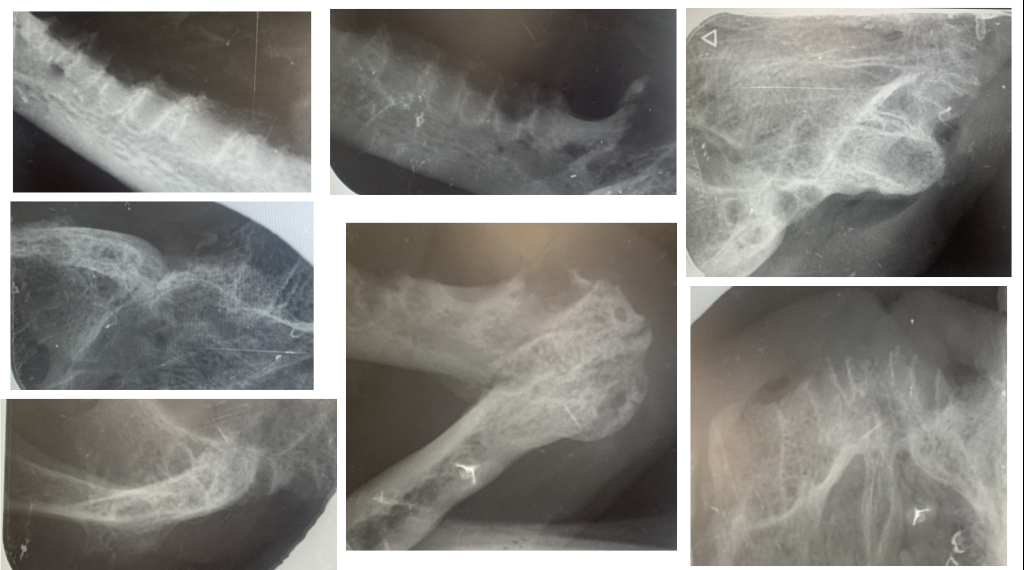

Основой лечения остается удаление всех премоляров и моляров с сохранением резцовой группы зубов и клыков, при этом важно, чтобы данные зубы не имели признаков воспаления и деструкции окружающих тканей как при инструментальном осмотре, так и на рентгенограммах.В случае выраженного воспаления или наличия деструктивных изменений может потребоваться полная экстракция зубов. Это позволяет устранить антигенную стимуляцию, вызванную налетом. Улучшение наблюдается в 60–80% случаев, однако 20–40% кошек нуждаются в дополнительном лечении5,6.

Однако недостаточно лишь удалить зубы пациенту, необходимо выполнить такую процедуру, как альвеолэктомия, – обязательное удаление периодонтальных связок и острых краев альвеолы для предотвращения остаточного воспаления. После альвеолэктомии накладываются швы на слизистую оболочку.

Лечение. Выполнены тотальное удаление зубов под контролем рентгенографии и альвеолопластика. Проведены кюретаж лунок и наложение швов (фото 4, 5).

Лечение. Проведены тотальное удаление зубов под рентгенологическим контролем, альвеолопластика, кюретаж и наложение швов (фото 10, 11).